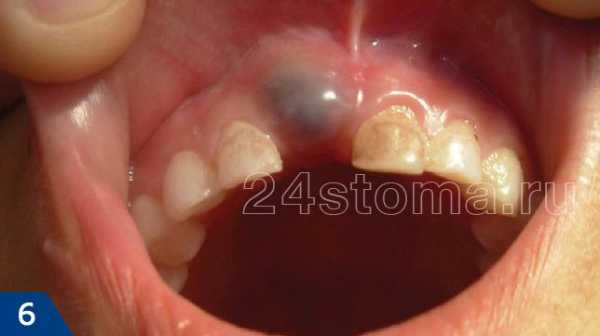

В некоторых случаях за 2-3 недели до прорезывания молочного или постоянного зуба на десне может появиться шишка, заполненная прозрачной или синюшной жидкостью (рис.6-7). Это не является патологией и не связано с воспалением. Каких-либо вмешательств (кроме периодического осмотра) не требуется. Только лишь в случае, когда шишка становится достаточно большой – можно сделать небольшой разрез и, таким образом, выпустить накопившуюся кровянистую жидкость.

Гематомы на слизистой оболочке десен –

в некоторых случаях десна при прорезывании зубов припухает и становится выраженного синюшного цвета (рис.6,7,11). Это обычно не требует вмешательства, и только если гематомы достигают больших размеров, то проводится маленький разрез с целью выпустить кровянистую жидкость.